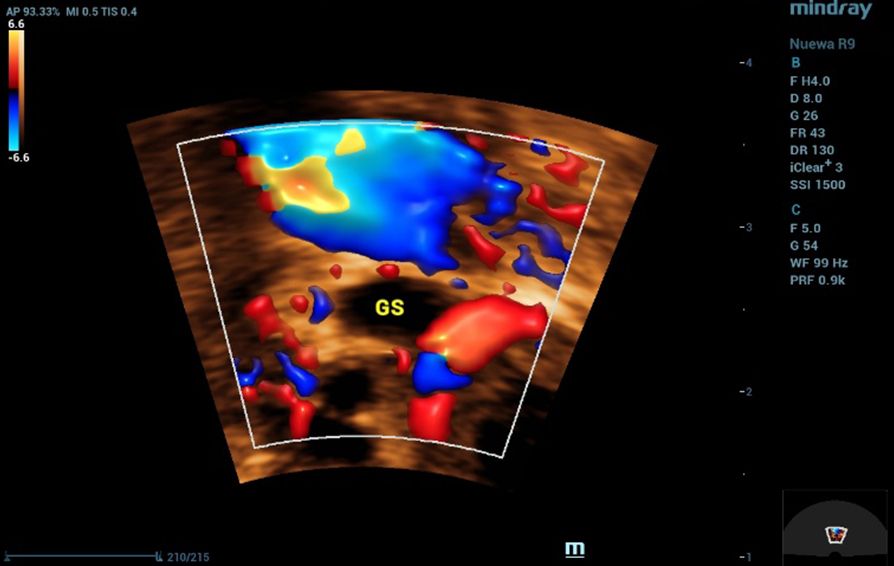

Diagnosis relies on a combination of serum ╬▓-hCG measurement and transvaginal ultrasound (TVUS), which is the imaging modality of choice. Typical ultrasound findings include the absence of an intrauterine pregnancy when ╬▓-hCG exceeds the discriminatory zone, an adnexal mass, or an extrauterine gestational sac with or without cardiac activity[4].?

Initial investigations included a urine pregnancy test, which returned positive. Transvaginal ultrasound was performed, revealing an anteverted, non-gravid uterus with no abnormal myometrial shadowing. The endometrium measured 14.2 mm.?

All ultrasound examinations were performed using the Nuewa R9 Ultrasound System (Mindray, Shenzhen, China). A convex transducer (SC6-1U) was employed for general pelvic evaluation, and a 4D transvaginal transducer (DE11-3WU) was used for detailed assessment of the uterus and adnexa. Imaging modalities included two-dimensional (2D) grayscale ultrasound, Color Doppler, and four-dimensional (4D) imaging.

To enhance diagnostic accuracy, advanced imaging applications were applied. Smart Endometrial Receptivity Analysis (Smart ERA) was utilized to assess endometrial morphology and volume, while the SCV+ function was employed to improve spatial resolution and delineation of adnexal structures. These features contributed to the precise characterization of the ectopic gestational sac and detailed evaluation of ovarian and endometrial parameters.

In this case, transvaginal ultrasound was central to the diagnosis. The examination revealed the absence of an intrauterine gestational sac despite a positive pregnancy test, a finding highly suggestive of ectopic pregnancy. Additionally, a small gestational sac was visualized outside the uterine cavity, confirming the diagnosis. These ultrasound findings, when correlated with the patientŌĆÖs symptoms of abdominal pain and vaginal spotting, highlight the critical role of transvaginal imaging in detecting ectopic pregnancies at an early stage, enabling prompt intervention and reducing the risk of complications.